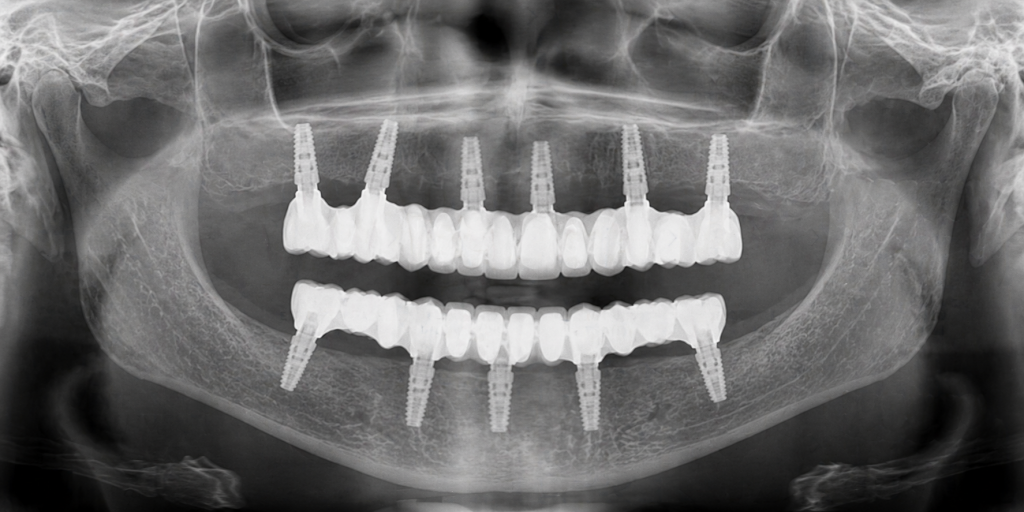

Perché a volte gli impianti sono inclinati

Non sempre l’osso è presente nelle zone ideali.

In alcune aree si riassorbe nel tempo, soprattutto dopo la perdita dei denti. Per questo motivo, in alcuni casi, gli impianti vengono inseriti con un’inclinazione specifica.

Non è una scelta casuale: serve per utilizzare al meglio l’osso disponibile, distribuire in modo equilibrato il carico masticatorio ed evitare, quando possibile, interventi più invasivi.

4 impianti o 6 impianti?

Il numero degli impianti non è una scelta commerciale. È una decisione clinica.

In alcune situazioni 4 impianti possono essere sufficienti per sostenere una protesi completa, in altre 6 impianti permettono una distribuzione più ampia dei carichi e una maggiore stabilità nel tempo.

La differenza non riguarda solo “quanti impianti”,

ma come la forza della masticazione viene gestita negli anni.